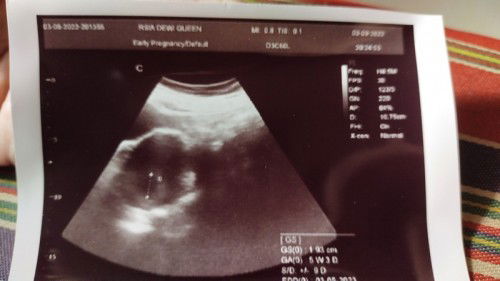

Usia kandungan

Selamat pagi bunda2. Maaf mau berbagi cerita Bund, kira2 ada yg sama dg saya tidak ya? Jadi, hpht saya 2 juli 2022, nah saya melakukan usg di dua dokter yg berbeda. Yg pertama saya melakukan usg pada tanggal 5 agustus, dan hasilnya usia janin 4 minggu 6 hari, itu benar kalo dihitung dari hpht. Dan usg yg ke dua dilakukan pada tanggal 3 september dg dokter yg berbeda, dan usianya baru 5 minggu 3 hari. Kata dokter, kemungkinan ini terjadi karena siklus haid tidak teratur, dan memang benar 6 bulan terakhir siklus saya tidak teratur. Kira2 apakah normal jika perbedaan usianya jauh dr hpht, apakah perkembangan janinnya normal ya Bunn?